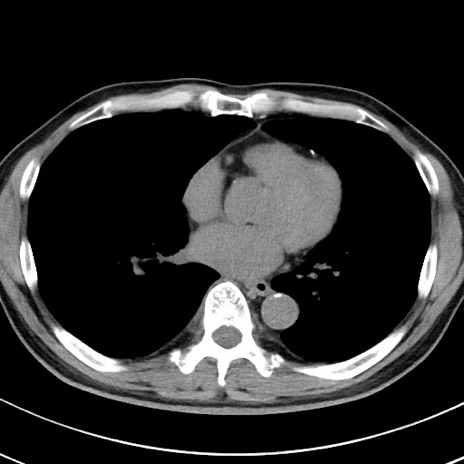

【腹部TIPS】症例29 参考症例 CT(横断像)

症例

70歳代男性